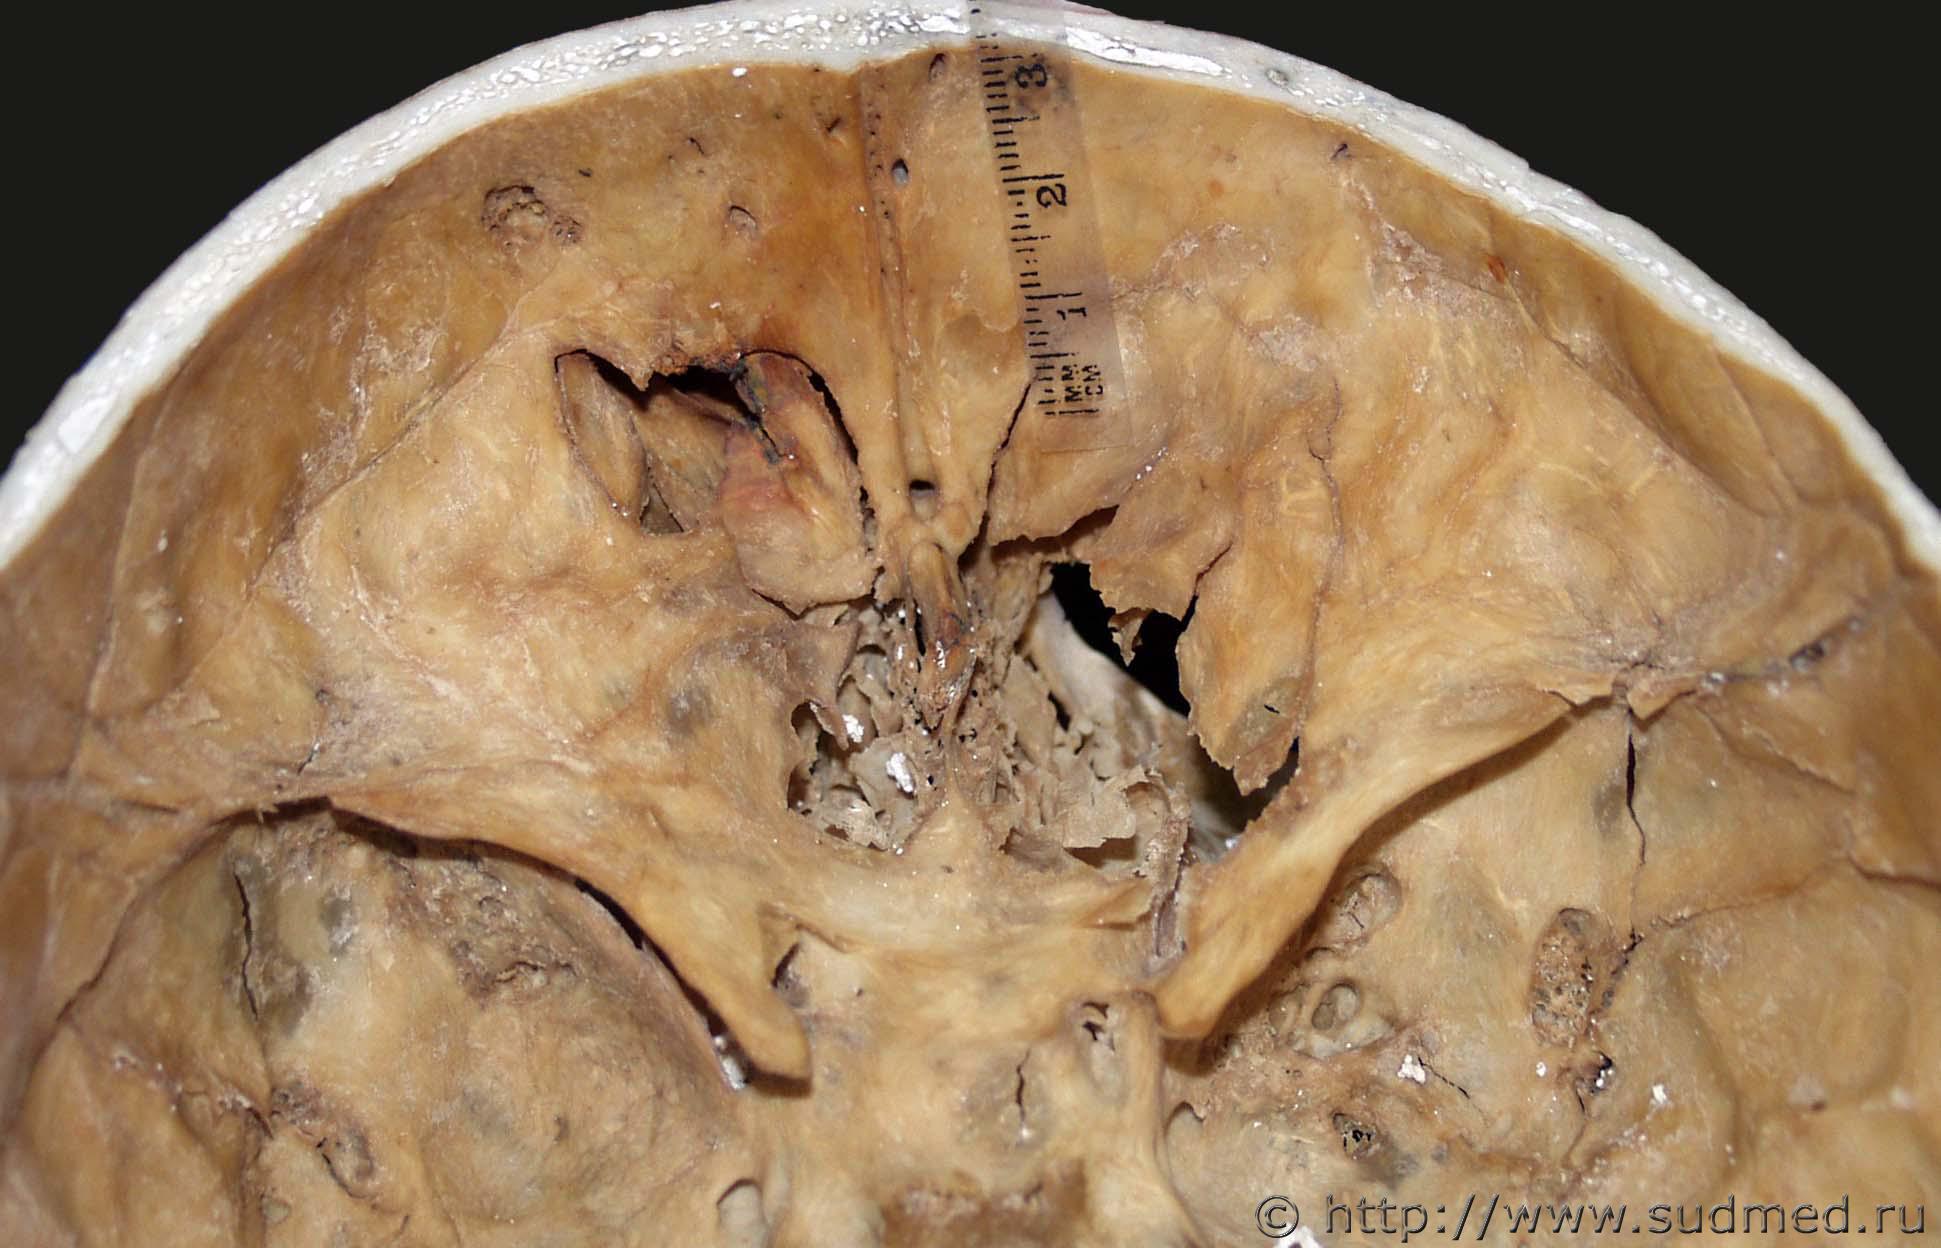

Диагностика сочетанного одиночного сквозного проникающего огнестрельного пулевого ранения шеи и головы по повреждениям на костях - в лесном массиве, за кольцевой автодорогой, были обнаружены скелетированные костные останки трупа молодой девушки (это установлено в ходе проведения остеологической идентификации).

Повреждения были обнаружены только на атланте, вид сверху Судебная медицина - Прикрепленное изображение, детально передняя дуга снаружи спереди Судебная медицина - Прикрепленное изображение и изнутри Судебная медицина - Прикрепленное изображение, основании черепа, вид снаружи Судебная медицина - Прикрепленное изображение и изнутри Судебная медицина - Прикрепленное изображение , и его своде, на левой теменной кости, вид снаружи Судебная медицина - Прикрепленное изображение и изнутри Судебная медицина - Прикрепленное изображение.

Детальный вид спереди снаружи снизу входного пулевого перелома передней дуги атланта и основной части затылочной кости после их совмещения Судебная медицина - Прикрепленное изображение.

Диагностика калибра пули проводилась по размерным характеристикам дефекта костной ткани между краями выходного дырчатого пулевого перелома со стороны внутренней костной пластинки и дополнительно иллюстрировалась результатами сравнительного исследования методом наложения - головная часть пули, вид сверху, штатного 9 мм патрона для стрельбы из ПМ или пистолета Стечкина Судебная медицина - Прикрепленное изображение и итоговое изображение одномасштабных совмещенных изображений перелома и головной части пули Судебная медицина - Прикрепленное изображение.

Пуля вышла из черепа боковым профилем, на что указывает форма и размеры дефекта между краями выходного дырчатого пулевого перелома левой теменной кости со стороны внутренней костной пластинки - проиллюстрировано сравнительным исследованием методом наложения - боковой профиль вышеуказанной пули Судебная медицина - Прикрепленное изображение и итоговое изображение одномасштабных совмещенных изображений перелома и бокового профиля пули Судебная медицина - Прикрепленное изображение. Дополнительно проводилось сравнительное исследование с пулей штатного 9 мм патрона для стрельбы из пистолета Люгера (P08, Parabellum) - Судебная медицина - Прикрепленное изображение и Судебная медицина - Прикрепленное изображение .

P.S. Личность погибшей установлена, преступление раскрыто, оружие ПМ, выстрел с близкой дистанции Судебная медицина - Прикрепленное изображение.